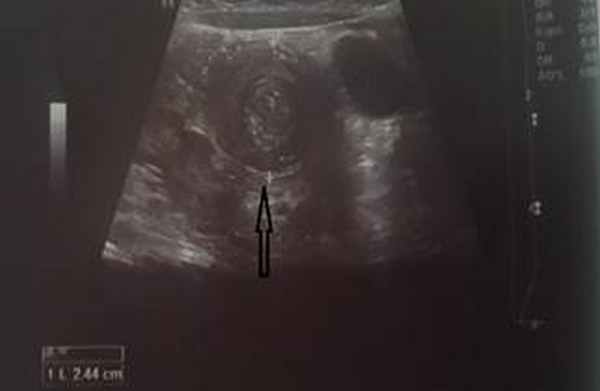

На рисунках 2 и 3 отображена ультразвуковая картина кишечной инвагинации.

Рис. 2. Симптом «мишени»

В момент УЗ-исследования врач может определить один из симптомов:

- симптом мишени (за счёт внедрения одной кишки в другую инвагинат на срезе выглядит как мишень);